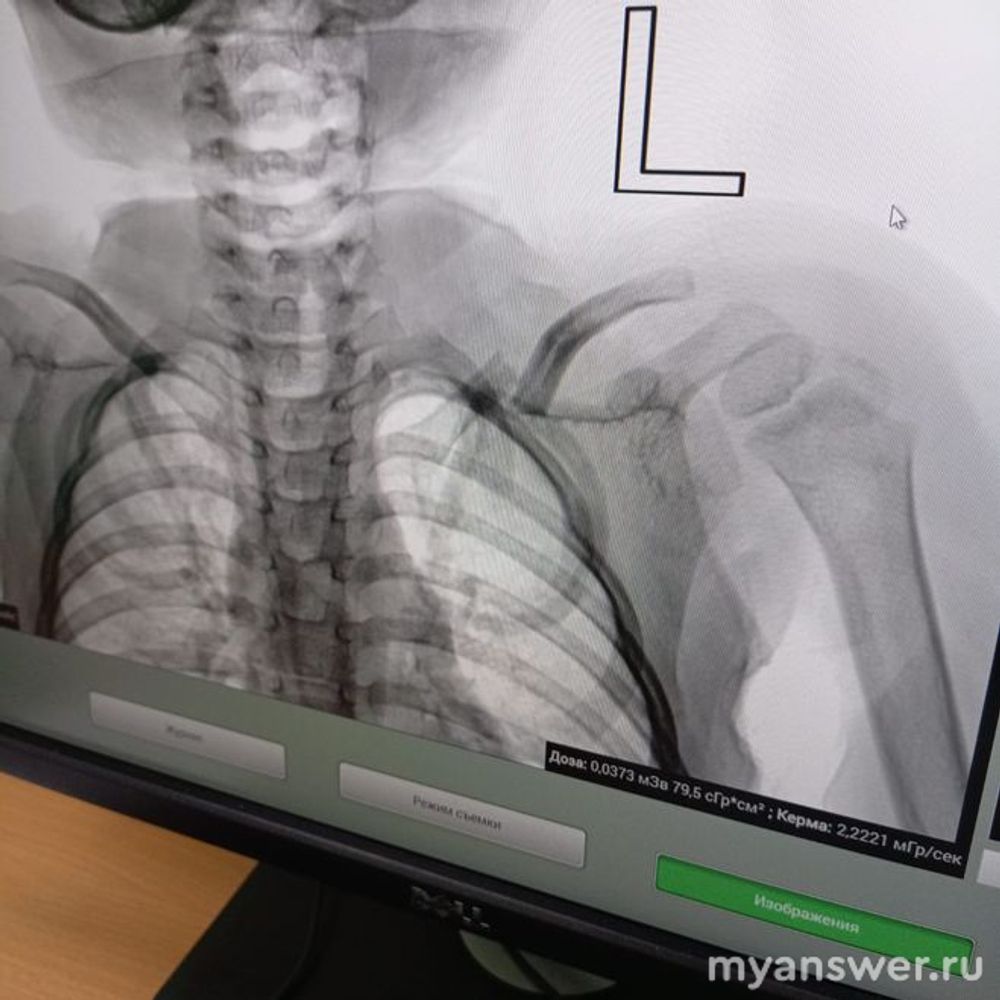

По своему многолетнему хирургическому опыты, могу сказать, отломки ключицы, даже не сопоставленные в основном не плохо срастаются и довольно быстро. Да, будет косметическая деформация, в области ключицы за счёт заметной костной мозоли, когда отломки срастаются не конец в конец, а бок в бок. Серьёзных нарушений функции плечевого сустава ожидать не приходится. В отношении выбора хирургического лечения неправильного стояния костных отломков значение будет иметь возраст пациента. В молодом возрасте, металлоостеосинтез перелома ключицы со смещением, имеет значение, а для пенсионера, сойдёт и так, как есть. Достаточно трёх недель походить с "кольцами", или повязкой "Дезо" из эластического бинта, это чтобы меньше болело. А дальше повреждение верхнего плечевого пояса само захочет работать. А для конкретики ответа, нужно видеть рентген снимок, на котором указывается и возраст больного.

Добрый день! Ребёнку один год и 11 месяцев

Насколько опасен невправленный перелом ключицы со смещением?